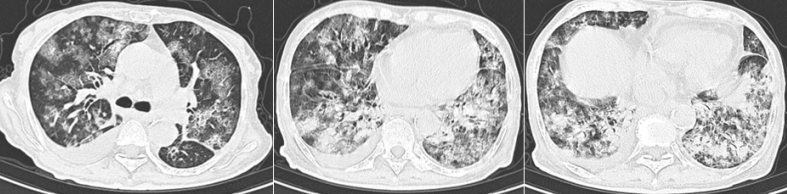

患者于外院行胸部CT示两肺多发渗出实变,地图样改变。于2022年8月1日行气管镜检查,肺泡灌洗液呈乳白色,NGS回报检出惠普尔养障体(序列数1163),人类冠状病毒229E(序列数778757)。外院予头孢匹胺等抗感染、抗病毒、激素抗炎等处理后症状改善不明显,遂转入我院急诊,就诊期间出现发热,体温波动在37.0~37.9℃之间,经我科会诊后拟“双肺弥漫性病变待查”收住监护室。血气分析(面罩吸氧15 L/min):pH 7.422,PaCO43.2 mmHg,PaO2 61 mmHg,BE/B 3 mmol/L,HCO328.2 mmol/L,SaO2 91%。外院胸部CT:双肺弥漫性磨玻璃影,斑片实变影,似乎有“地图征”样改变,还可见一些微小结节的影像,胸膜下有“黑带征”;纵隔窗未见纵隔淋巴结肿大,无特殊影像学表现(图1)

图片

图1  患者外院胸部CT